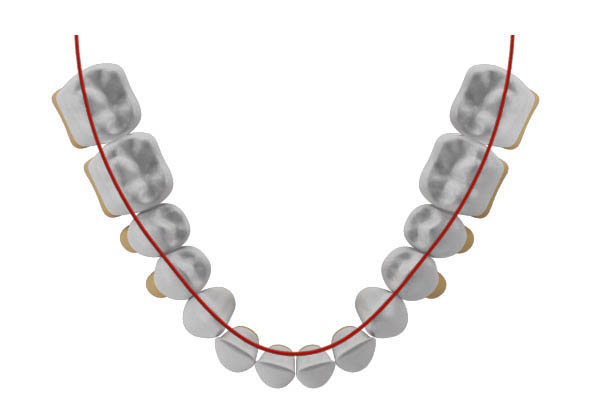

درشکل 40-2 قوس فکی را مشاهده میکنید.

اگر قدامیهای پائین سایز بزرگتری داشته باشند دو حالت رخ میدهد یا پروترود میشوند (شکل 41-2) یا اگر روی همان قوس باشند حالت کرادینگ خواهند داشت (شکل 42-2).

شکل 40-2: دندانهای بیمار درون قوس هستند

شکل 41-2: وقتی سایز قدامیهای پایین بزرگتر شود در قوس بزرگتری قرار میگیرند